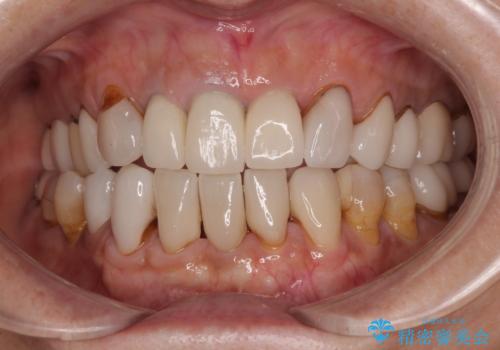

20年以上前から、むし歯になったり詰め物が欠けたりする度に部分的に処置を行ってきたそうですが、この際統一感のある前歯にしたいとのことで、上顎前歯9本をオールセラミッククラウンによる補綴治療を行うこととしました。

色調が統一されるだけでなく、歯肉ラインに見えていた茶色の境目も綺麗に改善されました。